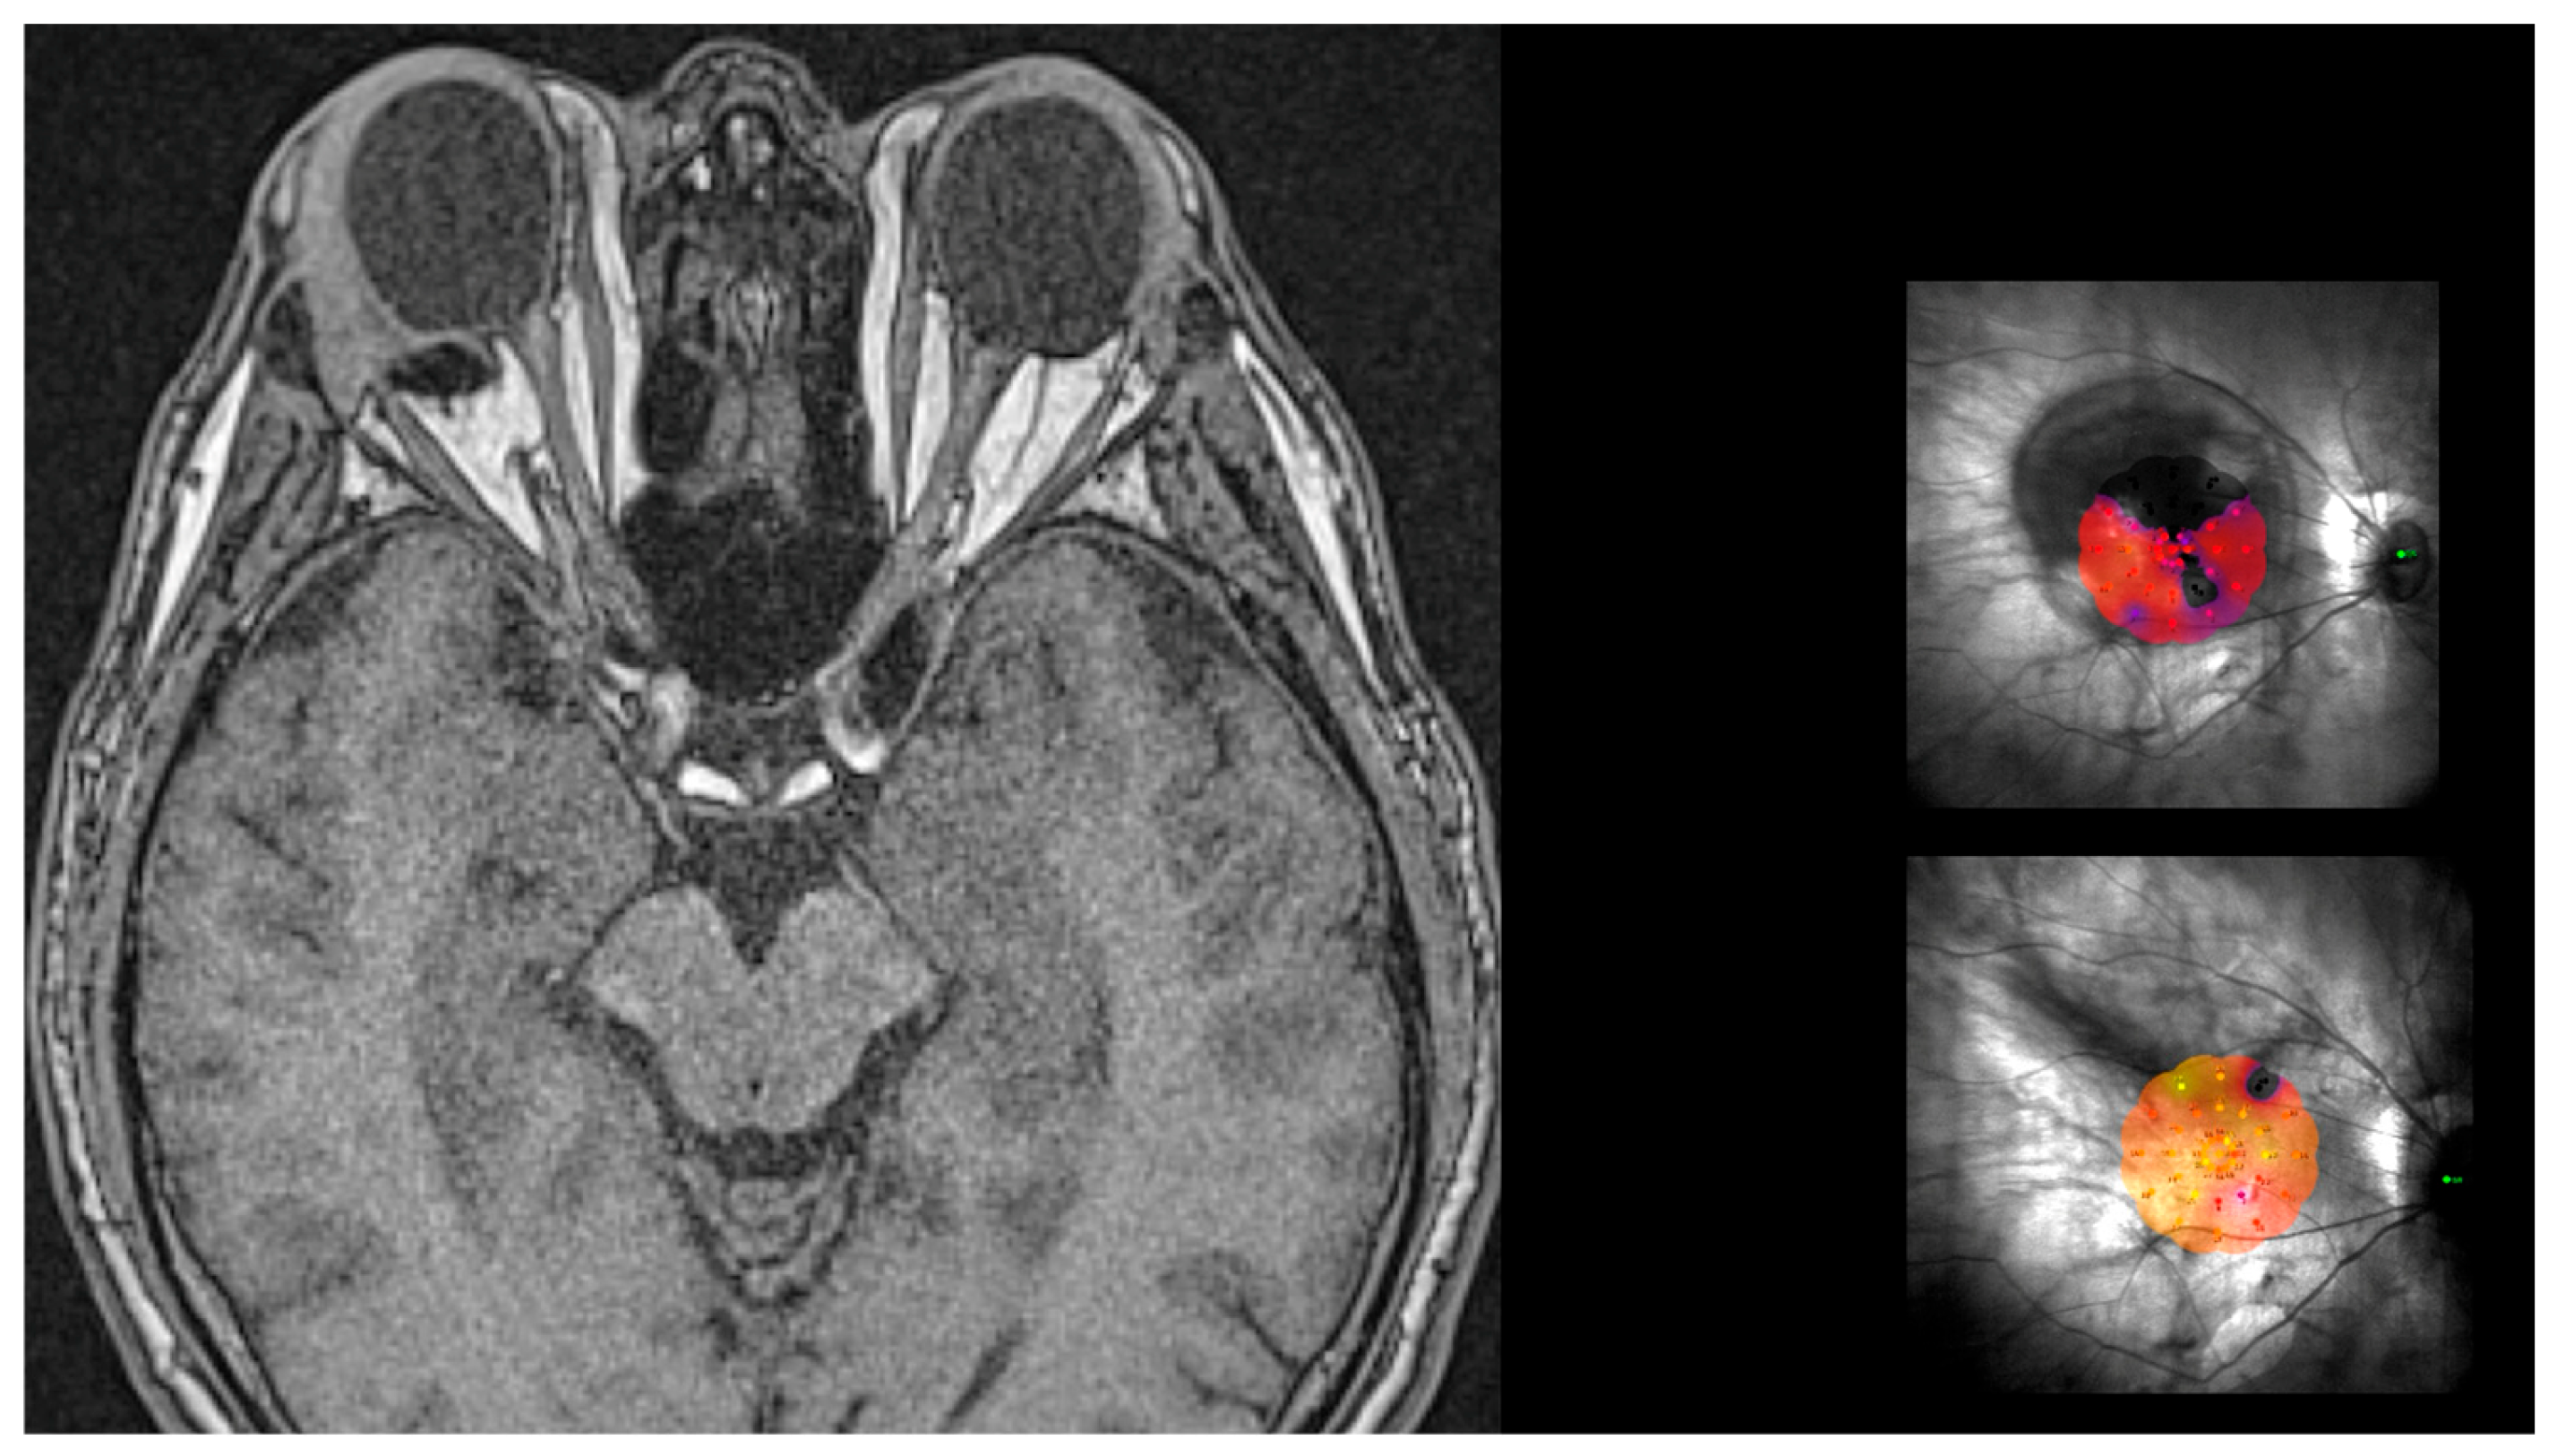

- Determining the DLN. The suture placement is the most important step of the whole surgery. The distance from limbus–needle (DLN) is marked to indicate where to enter with the needle to place the anterior superior and temporal sutures (Figure 4). Three points are marked with a caliper and staining, ideally marking the three corners of a triangle, with the apex at the limbus. The limbal point is marked at the 2:30 position in the left eye and at the 10:30 position in the right eye. The superior and temporal DLN points are marked according to the nomogram (described below).